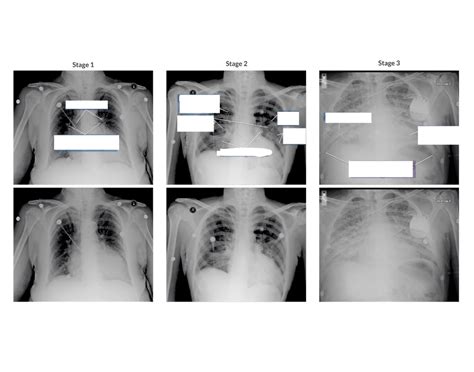

Key radiographic signs often appear in a specific sequence as the severity of the fluid overload progresses. Identifying these early can prevent the escalation to severe respiratory failure. The hallmark appearance is often referred to as "pulmonary congestion," which describes the initial phase of fluid accumulation.

There is a standardized progression of findings visible on a Pulmonary Edema Cxr. Recognizing these patterns allows for a systematic approach to diagnosis. The following findings are commonly documented in clinical reports:

• Cephalization: The redistribution of pulmonary blood flow to the upper lobes, which is one of the earliest signs of increased pulmonary venous pressure.

• Kerley B Lines: These are short, horizontal lines perpendicular to the pleural surface at the lung bases, representing thickened interlobular septa due to interstitial edema.

• Peribronchial Cuffing: This appears as a thickening of the bronchial walls, giving them a "donut" or "cuff-like" appearance on cross-section.

• Pleural Effusions: Fluid collecting in the pleural space, often bilateral but potentially unilateral, commonly seen in congestive heart failure.

• Bat-wing Opacities: In more severe cases, bilateral central alveolar opacities sparing the periphery of the lungs, indicating profound alveolar flooding.

Finding Clinical Significance Progression Level

Cephalization Increased pulmonary venous pressure Mild

Kerley B Lines Interstitial fluid accumulation Moderate

Alveolar Infiltrates Alveolar fluid flooding Severe